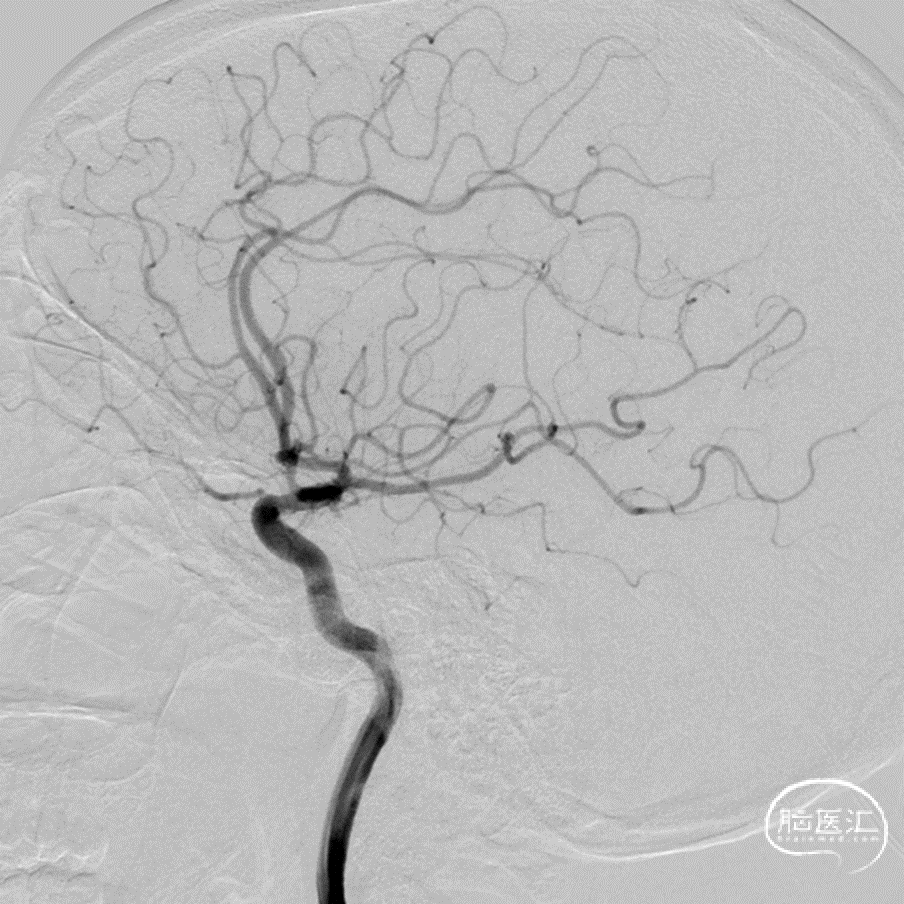

侧位造影

DSA三维重建

DSA:数值测量

脉络膜前动脉动脉瘤和真性脉络膜前动脉动脉瘤的鉴别,后者的位置距离脉络膜前动脉和颈内动脉的连接处有一段距离